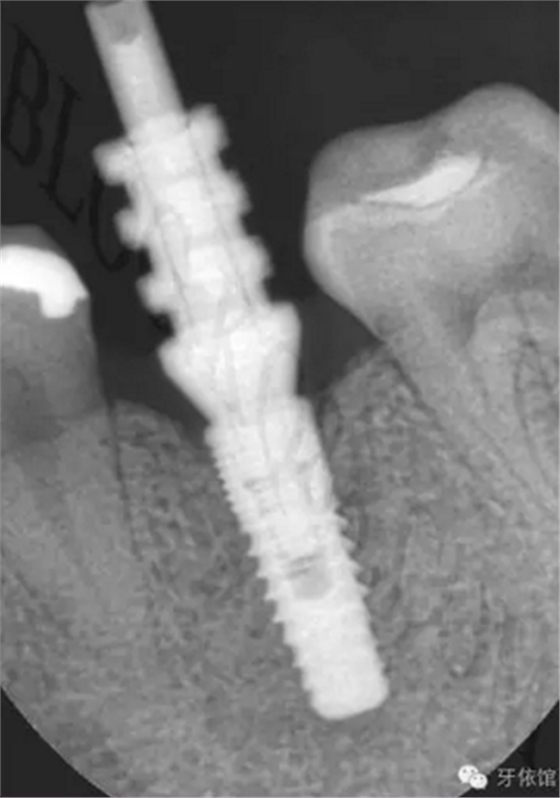

患者:女,28歲,此x光片為4年前拍的,左下6已于四年前行種植修復(fù),今天主要介紹右下6種植修復(fù)過程。計劃微創(chuàng)種植。

右下6口內(nèi)照片顯示牙槽嵴頂寬度并不是很充足,微創(chuàng)種植有一定的風(fēng)險,跟患者協(xié)商后,同意微創(chuàng)種植。

連接印模帽后拍x光片,檢查印模帽與種植體之間是否緊密相連。